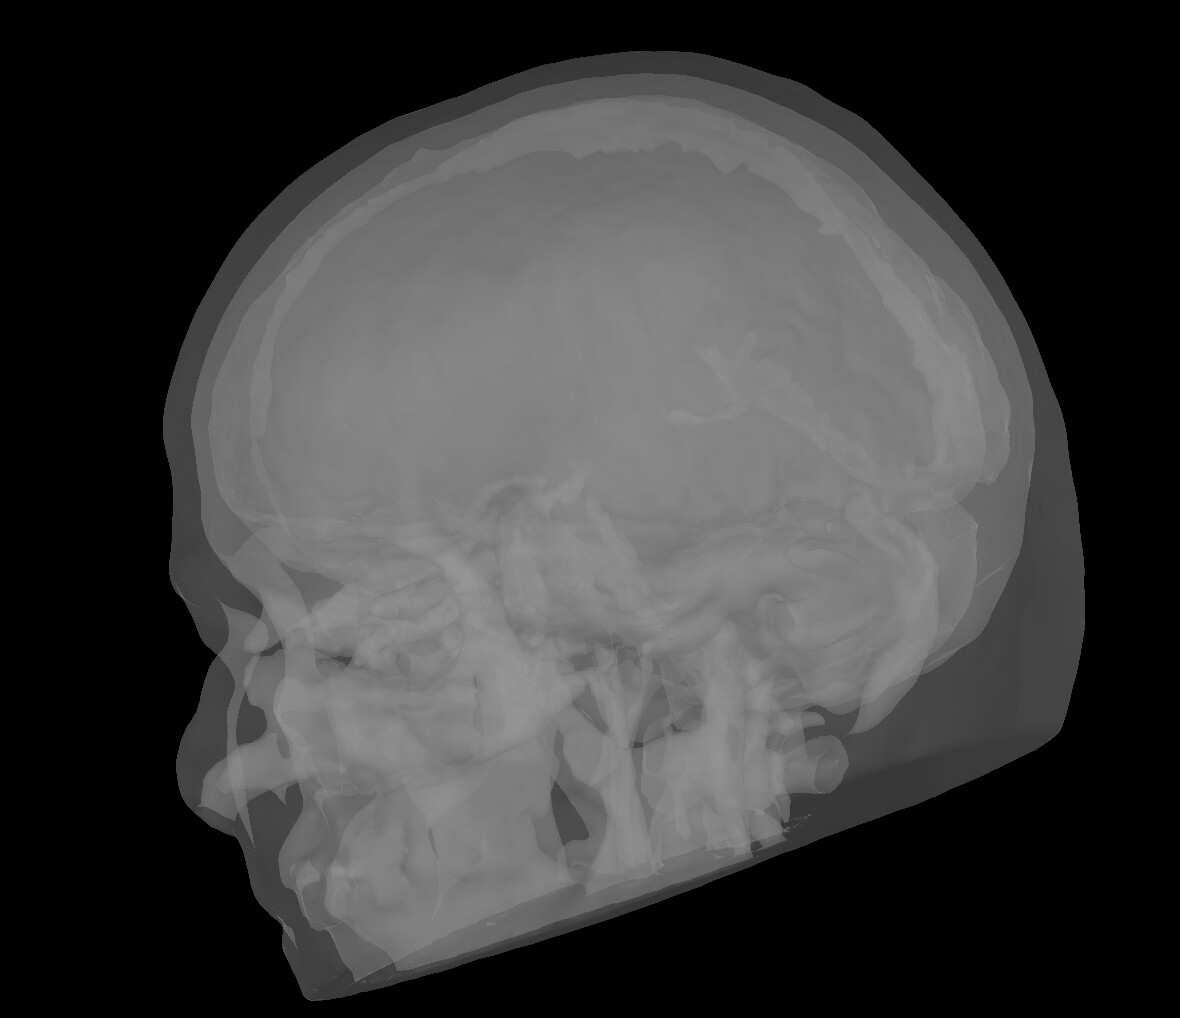

As a matter of fact, while the FEM model seems to do a good tissue characterisation, all the surfaces I have extracted within Brainstorm are wrong. For example, the scalp seems to have some skull embedded within

or, for example, the skull seems the CSF(?)